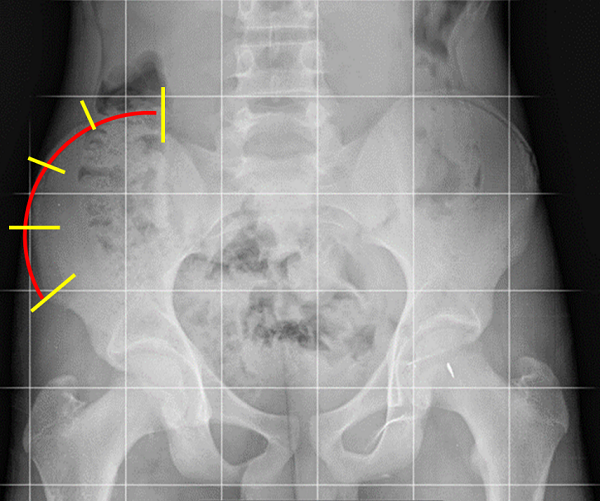

Cada curva se define entre dos vertebras, al inicio y al final de esta. Son las “vértebras límite”, las cuales se identifican como aquellas a partir de las cuales la curva cambia de dirección y, por ende, tienen la mayor inclinación hacia el lado cóncavo de la escoliosis. Se eligen de tal manera que entre ellas formen el mayor ángulo posible y corresponden a aquellas con la superficie del platillo vertebral más inclinado hacia la concavidad (Figura 9).

Figura 9. Angulo de Cobb e índice de Moe de la escoliosis. El ángulo de Cobb se determina entre las dos vértebras que están más inclinadas hacia la concavidad, límites a su vez de la curva escoliótica. El índice de Moe valora la imagen asimétrica de los pedículos y da información de la importancia de la rotación de la vértebra ápex. Mostrar/ocultar

Existen distintas formas de medir el ángulo de esta curva, pero el más frecuente es el ángulo de Cobb. Este ángulo está definido entre dos líneas que pasan, una de ellas paralela por el platillo superior en la vértebra límite superior y la otra por el platillo inferior de la vértebra límite inferior.

Normalmente en el centro de la curva se localiza la vertebra ápex (aunque a veces el ápex de la curva es un disco intervertebral). Corresponde al punto con mayor desplazamiento lateral desde eje central de la columna. Es la vértebra más deformada, la que está más rotada. En esta vértebra se mide el índice de Moe que determina la situación, más o menos centrada, de los dos pedículos (Figura 9). Cuanto más en el ápex y cuanto más rotada, el índice de Moe es mayor porque la vértebra proyecta los pedículos en posición asimétrica. Las apófisis espinosas también se deforman apuntando a la concavidad.